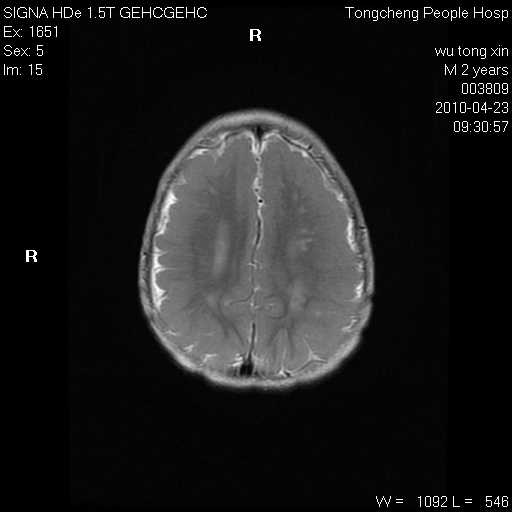

以下是引用赵物学在2010-4-25 12:43:00的发言:[br]巨脑回[br]侧脑室后角低密度影考虑hie或肾上腺脑白质营养不良?[br][br][本贴已被 赵物学 于 2010-4-25 12:51:28 修改过]

以下是引用gaoxiao在2010-4-25 16:54:00的发言:[br]巨脑回畸形。脑白质髓鞘化不良

以下是引用pujunzhi在2010-4-25 21:35:00的发言:[br]考虑 1双侧大脑皮质发育不良 2轻度脑积水 3双侧脑室后角旁片状长t1长t2信号,需继续观察,因为正常小儿此处脑白质的髓鞘化时间可以延迟到4-6岁,才显示正常。